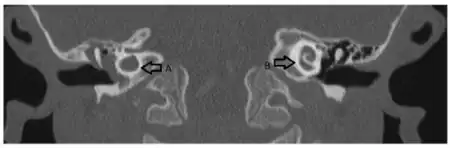

| a)Dysmorphic cochlea in right ear (A) and the normal cochlear structure in other ear | |

This deformity was first described in 1791 by Mondini after examining the inner ear of a deaf boy. The Mondini dysplasia describes a cochlea with incomplete partitioning and a reduced number of turns, an enlarged vestibular aqueduct and a dilated vestibule. A normal cochlea has two and a half turns, a cochlea with Mondini dysplasia has one and a half turns; the basal turns being normally formed with a dilated or cystic apical turn to the cochlear. The hearing loss can deteriorate over time either gradually or in a step-wise fashion, or may be profound from birth.[1]